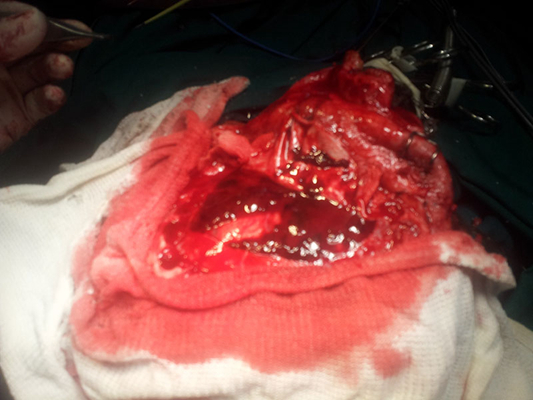

顱內血腫圖片

硬膜下血腫 (7)

硬膜下血腫 (8)

硬膜下血腫 (9)